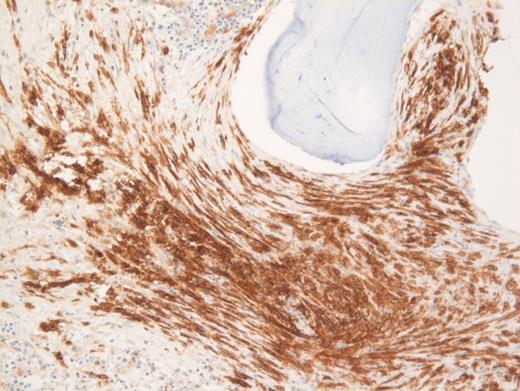

These results prompted a subsequent bone marrow biopsy. Peripheral blood smear showed rare abnormal circulating cells (Figure 1). Bone marrow core biopsy showed clusters of spindle cells adjacent to bony trabeculae (Figure 2) that were positive for CD117 (Figure 3). Scattered teardrop cells were also noted. Molecular testing by next-generation sequencing (NGS) detected diagnostic mutations.

Mast cell with metachromatic granules in circulation (Figure 1) with spindly clusters of compact mast cells in the biopsy (Figure 2) that are positive for CD117 (Figure 3) allows a diagnosis of systemic mastocytosis. These marrow spindly clusters of cells were also positive for mast cell tryptase and CD25. Mastocytosis is defined as multifocal infiltration by clonal proliferation of mast cells in one or more sites. They are broadly divided into cutaneous mastocytosis, systemic mastocytosis (SM), and mast cell sarcoma. The 2016 World Health Organization (WHO) classification of hematologic neoplasms separated them from myeloproliferative neoplasms. Cutaneous mastocytosis is restricted to the skin.

Neoplastic mast cells often assume a spindle shape on biopsy. All mast cells co-express CD117 and mast cell tryptase. However, when they express CD25, SM should be suspected. The mast cells in this case were positive for CD117, tryptase, and CD25 (not shown).

Of the choices provided, only SM is positive for CD117. Langerhans cell histiocytosis usually shows some admixed eosinophils, and furthermore, they are positive for CD1a and langerin and negative for CD117. Spindle cells in melanoma metastasis are positive for S100 and SOX10 and negative for CD117. Fibrosis is usually diffuse and not patchy in primary myelofibrosis, and furthermore, these areas negative for CD117. Also, circulating mast cells would be inconsistent with primary myelofibrosis, melanoma, or Langerhans cell histiocytosis.